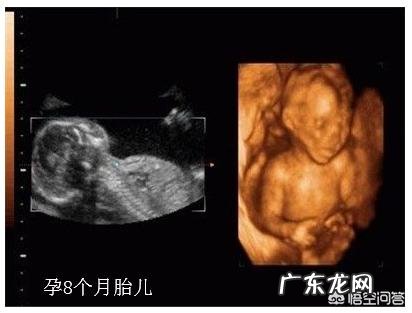

一、胎儿情况胎儿长约43-45cm,重约1.3-2.0kg,此时胎儿的内脏器官和脑、神经系统发展到了一定程度,肺和胃肠功能已接近成熟,已具备呼吸能力,能分泌消化液;胎儿皮下脂肪正在快速囤积,胎儿胎动越来越频繁,但是随着孕期增加,受宫内空间限制,胎动幅度、频率会降低 。